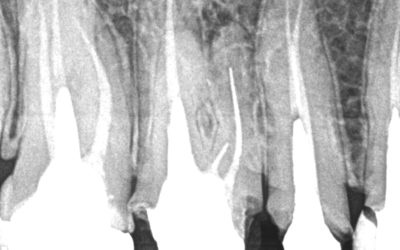

Dente 16 - Remoção de peça, pino metálico, limas fraturadas nos canais mv, mv2 e dv.Para a remoção de lima fraturada ou qualquer outro instrumento endodôntico fraturado dentro do canal, o mais importante de todos os equipamentos utilizados é o...